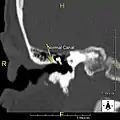

Normal ear canal